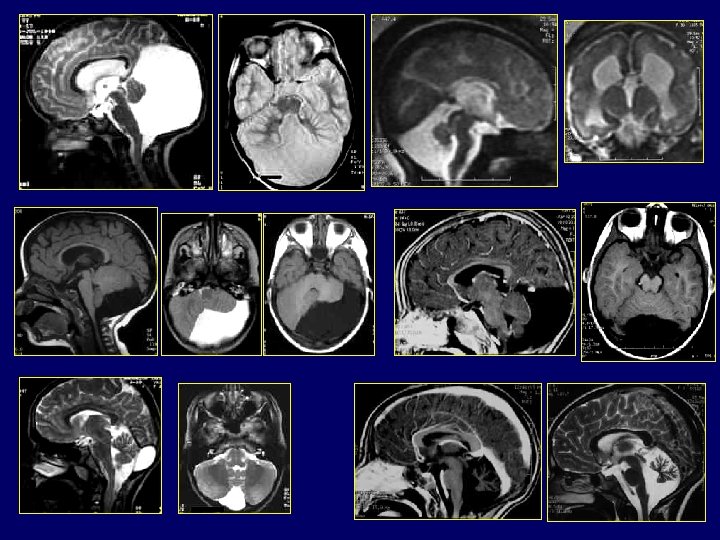

Malformations fosse postérieure complexe Dandy Walker • Hémisphères cérébelleux incomplètement formés >>>Vermis partiellement agénésique • Toile choroïdienne non perforée >> Hydrocéphalie sus jacente >>>>Malformation Dandy Walker • Toile choroïdienne perforée >>Absence d’hydrocéphalie >>>>Malformation Dandy Walker variant • Toile choroïdienne mal ouverte + cervelet normal >>Poche sus et rétro-cérébelleux: Poche de Blake

Malformations fosse postérieure complexe Dandy Walker Malformations kystiques : historiquement les plus connues ne résument pas la pathologie malformative Malformation de DW : • Élargissement de la fosse postérieure • Déplacement vers le haut des sinus latéraux, de la tente et du torcular • Dilatation kystique du V 4 • Hypoplasie ou agénésie vermienne +/compléte Diagnostic prénatal facile +++ explique la de la fréquence • L'IRM permet d'authentifier ce reliquat vermien, d'apprécier sa rotation sous la poussée du V 4 dilaté, d'étudier le retentissement de cette dilatation sur le tronc cérébral et la perméabilité de l'aqueduc de Sylvius

• DW variant : – Agénésie partielle ou hypoplasie – Dilatation kystique du V 4 – Absence d’élargissement de la fosse postérieure – Élément important +++. Nature des malformations cérébelleuses et des anomalies sus tentorielles associées. • Méga grande citerne : – Fosse postérieure élargie, liquidienne – Normalité du vermis / HC / pont – Diagnostic différentiel : KA rétro ou sous cérébelleux mais peu d’implications pronostiques ou pratiques